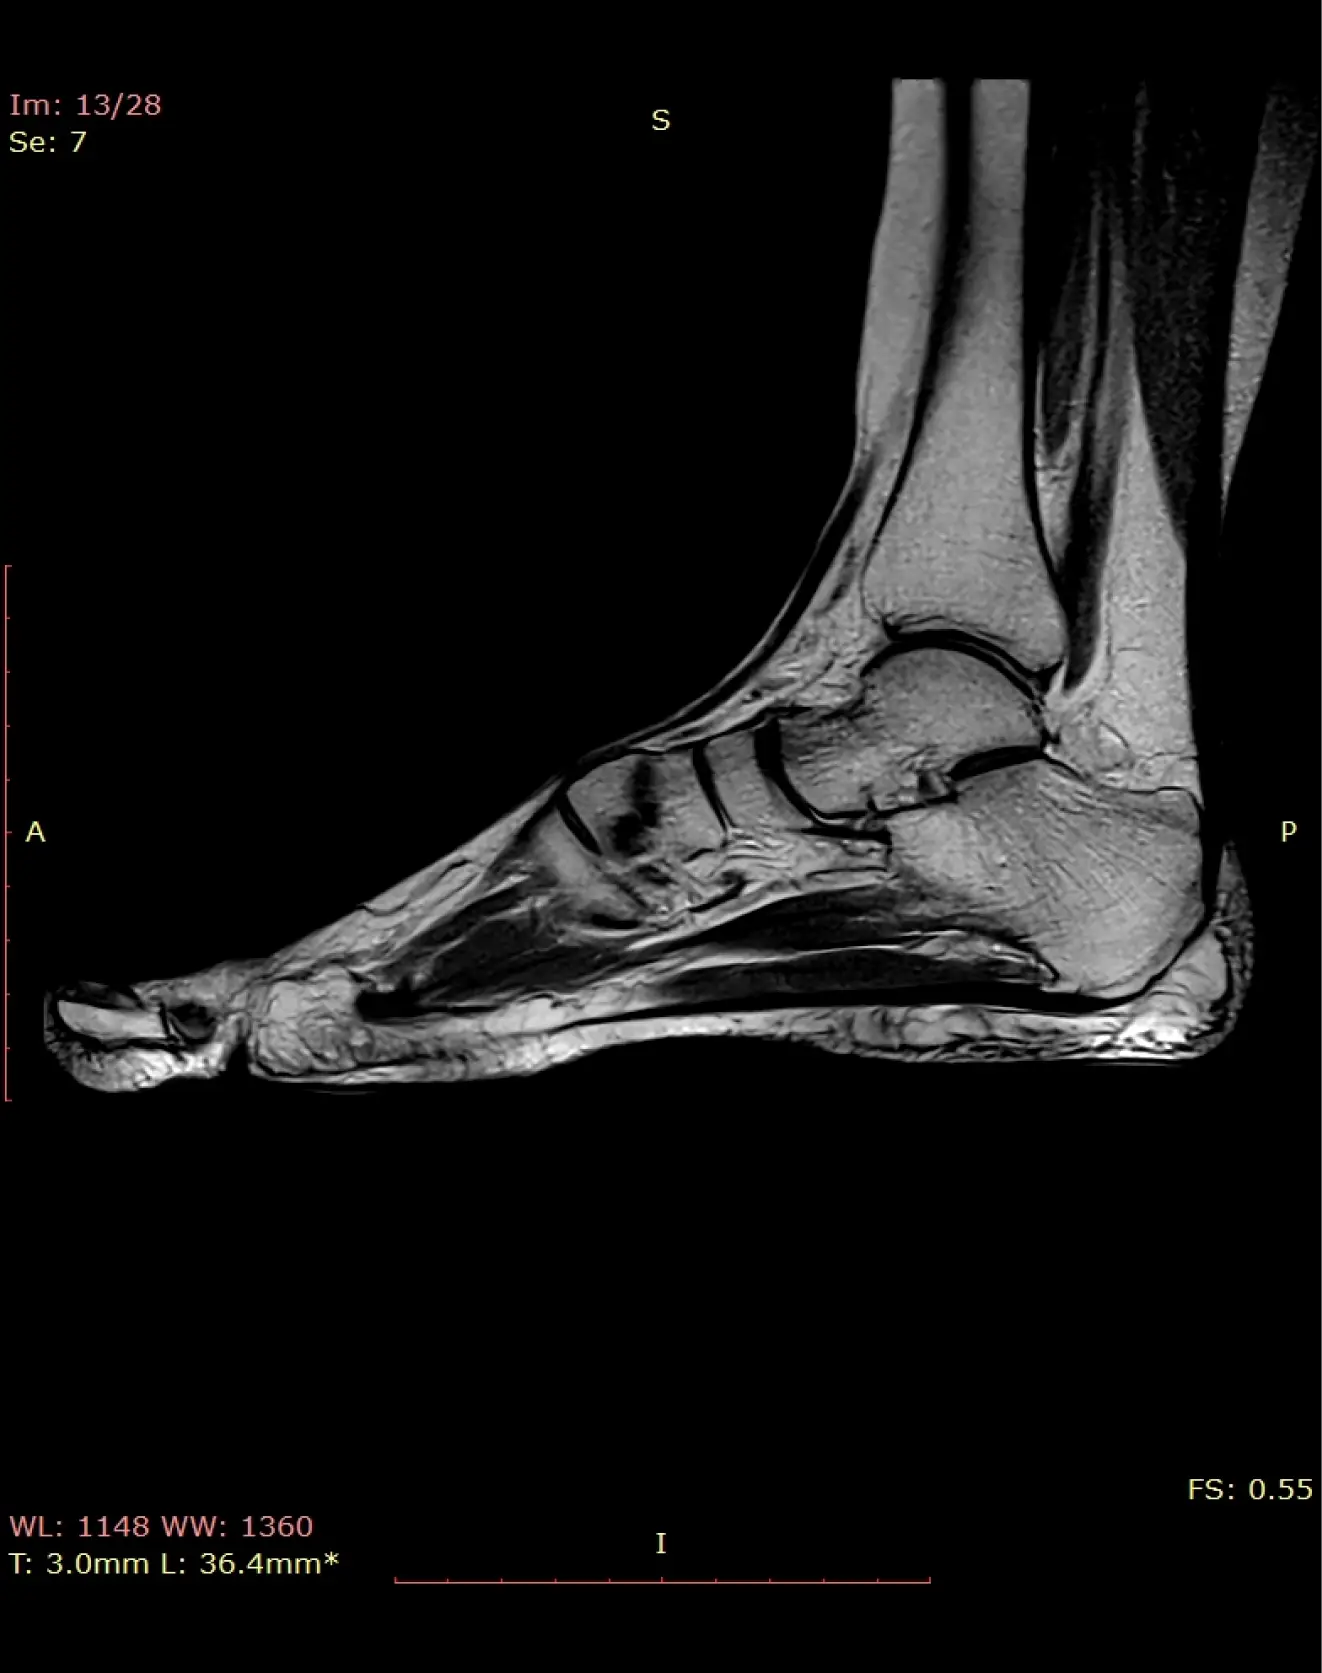

МРТ стопы

Помимо голеностопного сустава, визуализируются структуры предплюсны, плюсны и фаланг, включая сочленения, сухожилия, мягкие ткани (айхиллово сухожилие, плантарная фасция и т.д.).